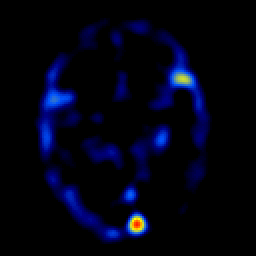

overlay -- Slice #12

[Home][Help][Clinical] Slice 12